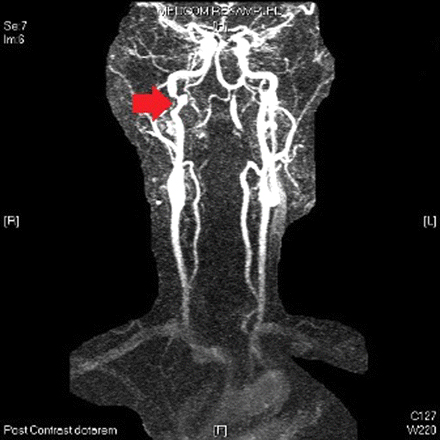

Duplex ultrasound, computed tomography angiography, or magnetic resonance angiography may show the intimal flap and intramural thrombus.[Figure caption and citation for the preceding image starts]: Magnetic resonance time of flight image of brain. The arrow shows the right carotid artery with a crescent-shaped appearance. This is consistent with intramural haematoma consequent upon dissection of the right carotid arteryUsed with permission from BMJ Case Reports 2012; doi:10.1136/bcr.01.2012.5636 [Citation ends].